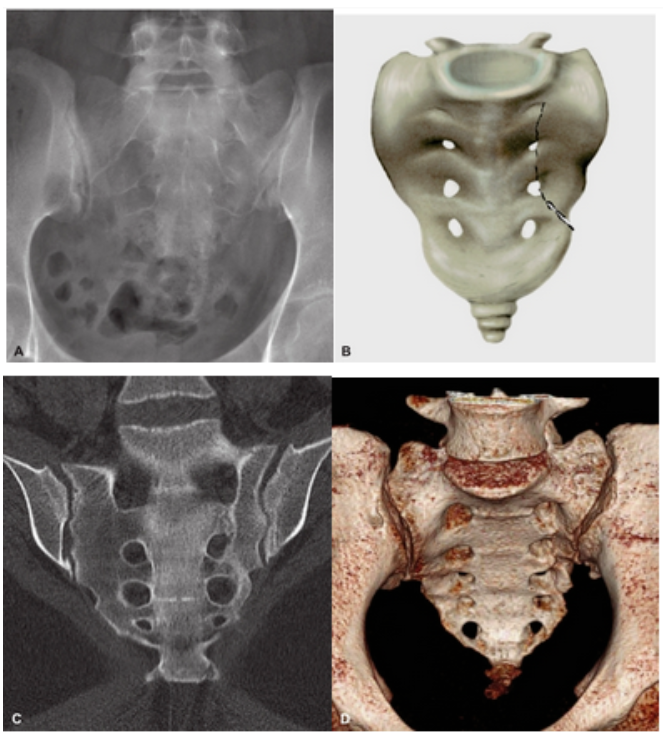

3D成型机和生物力学仿真工作站软硬件设备:

基于医学影像技术、生物力学、人机工程学建立用于模拟人体肌肉骨骼和视听系统仿真计算分析平台。